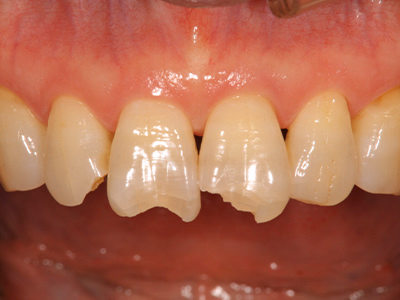

前歯(コンポジットレジン)

治療前後写真

治療前

治療後

33歳・女性

転倒で前歯の切端が破折

マイクロスコープ+ラバーダム下で3色レジンを積層接着

再破折予防にナイトガード作製

治療期間

費用

リスク・副作用

医院コメント

色調再現と形態回復を同時に達成し、機能・審美を短期に改善。